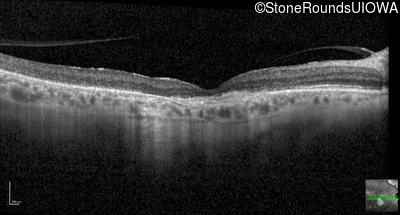

Optical Coherence Tomography - Right - 20/80

Exemplar / OCT Stack